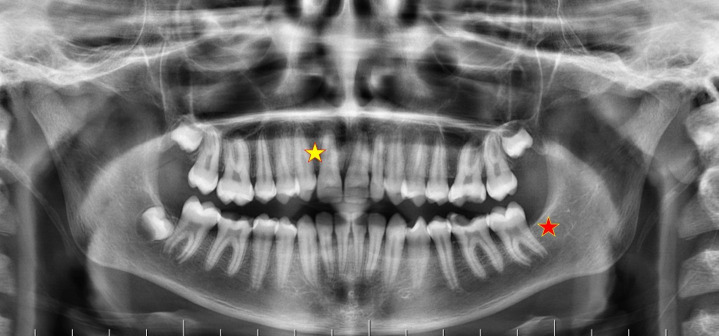

Objectives: Dental agenesis refers to the absence of one or more teeth, occurring in both primary and permanent dentitions. It can result in several complications, impacting functional aspects of the dentition, such as chewing and speech. This study aimed to evaluate the prevalence of agenesis of permanent incisors, premolars, and third molars in patients aged 8-18. The prevalences were compared according to age, gender, and the regions they live in.

Material and methods: This study was conducted in the Central Anatolia and Mediterranean regions of Turkey. It included data from 593 patients, 304 females and 289 males. The study involved a retrospective evaluation of the patients' orthopantomographic images. Descriptive statistics were employed for the analysis.

Results: In the study, the prevalence of incisor agenesis among all patients was 2.4%. Premolar agenesis was found in 3.9% of patients, with the mandibular second premolar being the most commonly missing premolar (missing in 19 patients). The prevalence of third molar agenesis was 19.9% (118 patients). Incisor and premolar agenesis were more common in the Central Anatolia region than the Mediterranean region, whereas third molar agenesis was more prevalent in the Mediterranean region. In both regions, the left mandibular premolar was the most frequently missing premolar tooth, and the left maxillary third molar was the most frequently missing third molar tooth.

Conclusion: This study presents a thorough analysis of the prevalence and distribution of tooth agenesis, with a particular focus on incisors, premolars, and third molars. The results emphasize the necessity of considering gender differences and specific tooth locations in the diagnostic and therapeutic approaches to tooth agenesis.